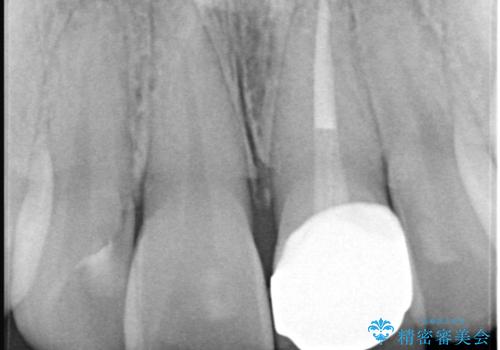

精密な再根管治療: 古い充填材を除去し、歯科用顕微鏡を用いて根管内を徹底的に清掃・殺菌しました。根の先まで確実に薬剤を詰め直すことで、将来的な根尖病変(根の先の膿)のリスクを最小限に抑えました。

土台(ファイバーコア)の構築: 金属の土台は将来的な変色の原因となるため、光の透過性が高く、歯のしなりに近い性質を持つファイバーコアを採用。これにより、被せ物の透明感を損なわず、歯の破折も防ぎます。